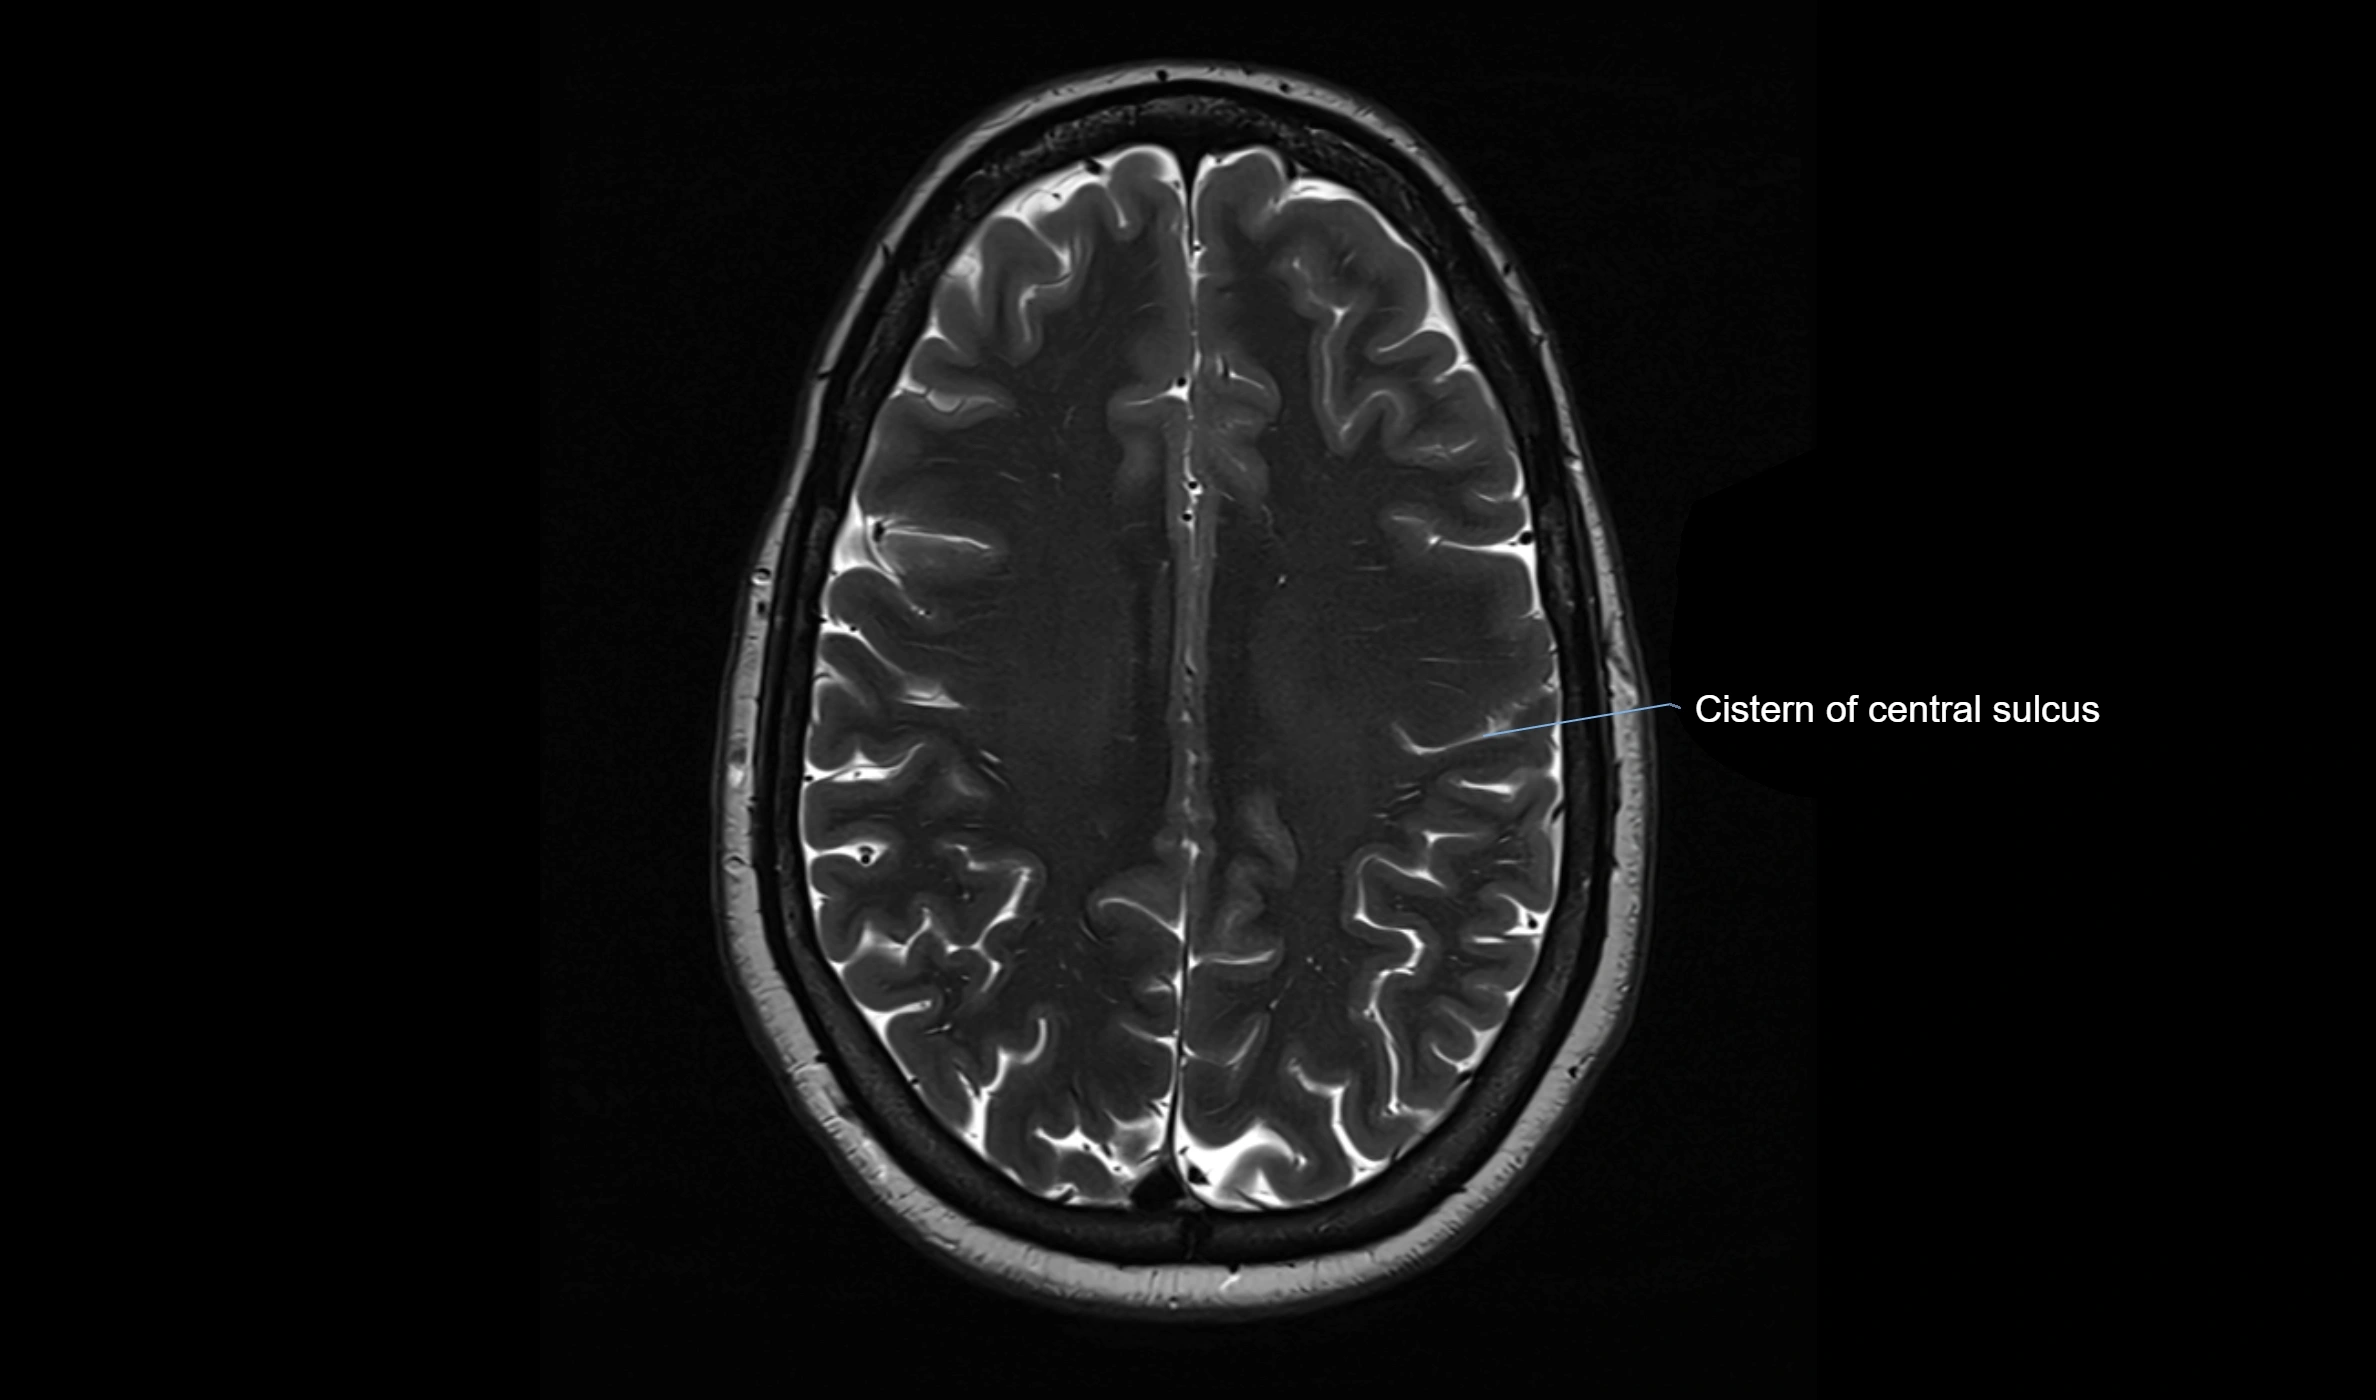

MRI images

image